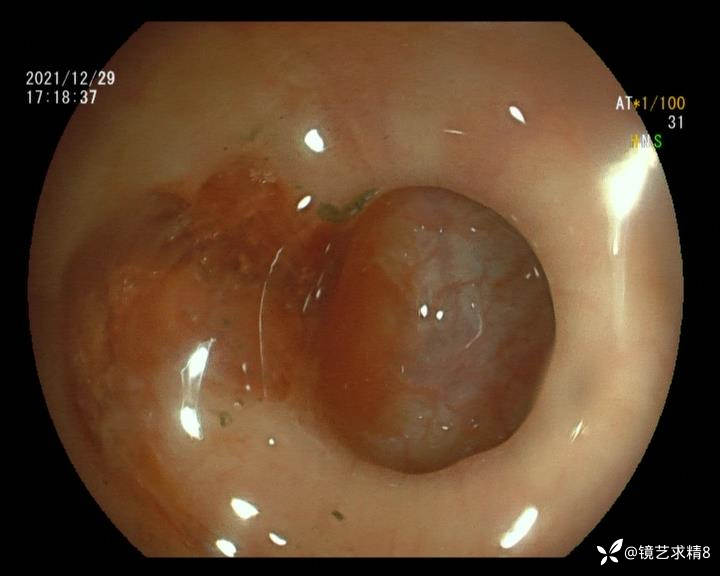

结肠内违建⥤结肠多发憩室☞续

小壮兵爱学习等 2人推荐看到手机存有2年前一个病例仅有的3张图片,因为没有更多的图片就只描述了多发憩室这个内容,没想到浏览量很快上万,很多都和我一样第一次见这么多憩室的结肠,就不得不想要把2年前所有的片子拷贝出来分享。该病例憩室合并外源性因素成为憩室出血的原因。后面附有代表性的全结肠图片。

患者以消化道出血入院,胃镜未见异常,肠镜进入乙状结肠就看到很多憩室,同时还看到肠腔用清肠药后移动下来1枚尖锐的枣核,这么多憩室,这个枣核扎入憩室的机会非常大,推测应该是掉入一坑🕳就算出来还会有很多坑🕳🕳🕳等着,掉入憩室内很容易刺破血管,这可能就是消化道出血的原因,继续前进可以看到有一些憩室内翻,还有一些息肉,问题来了,那么多憩室,犯罪分子是抓住了,它在那些憩室内作过案?到达回盲部后挨个冲洗,但憩室大小又不足以把镜头进入憩室内观察,针对有血块的憩室冲洗后可疑出血的以夹子闭合或套扎,取出枣核,如果有锥形透明帽可能钻入憩室精准电凝效果更好,若内镜下操作失败介入治疗成功率更高,经内镜下治疗后观察未再出血出院。